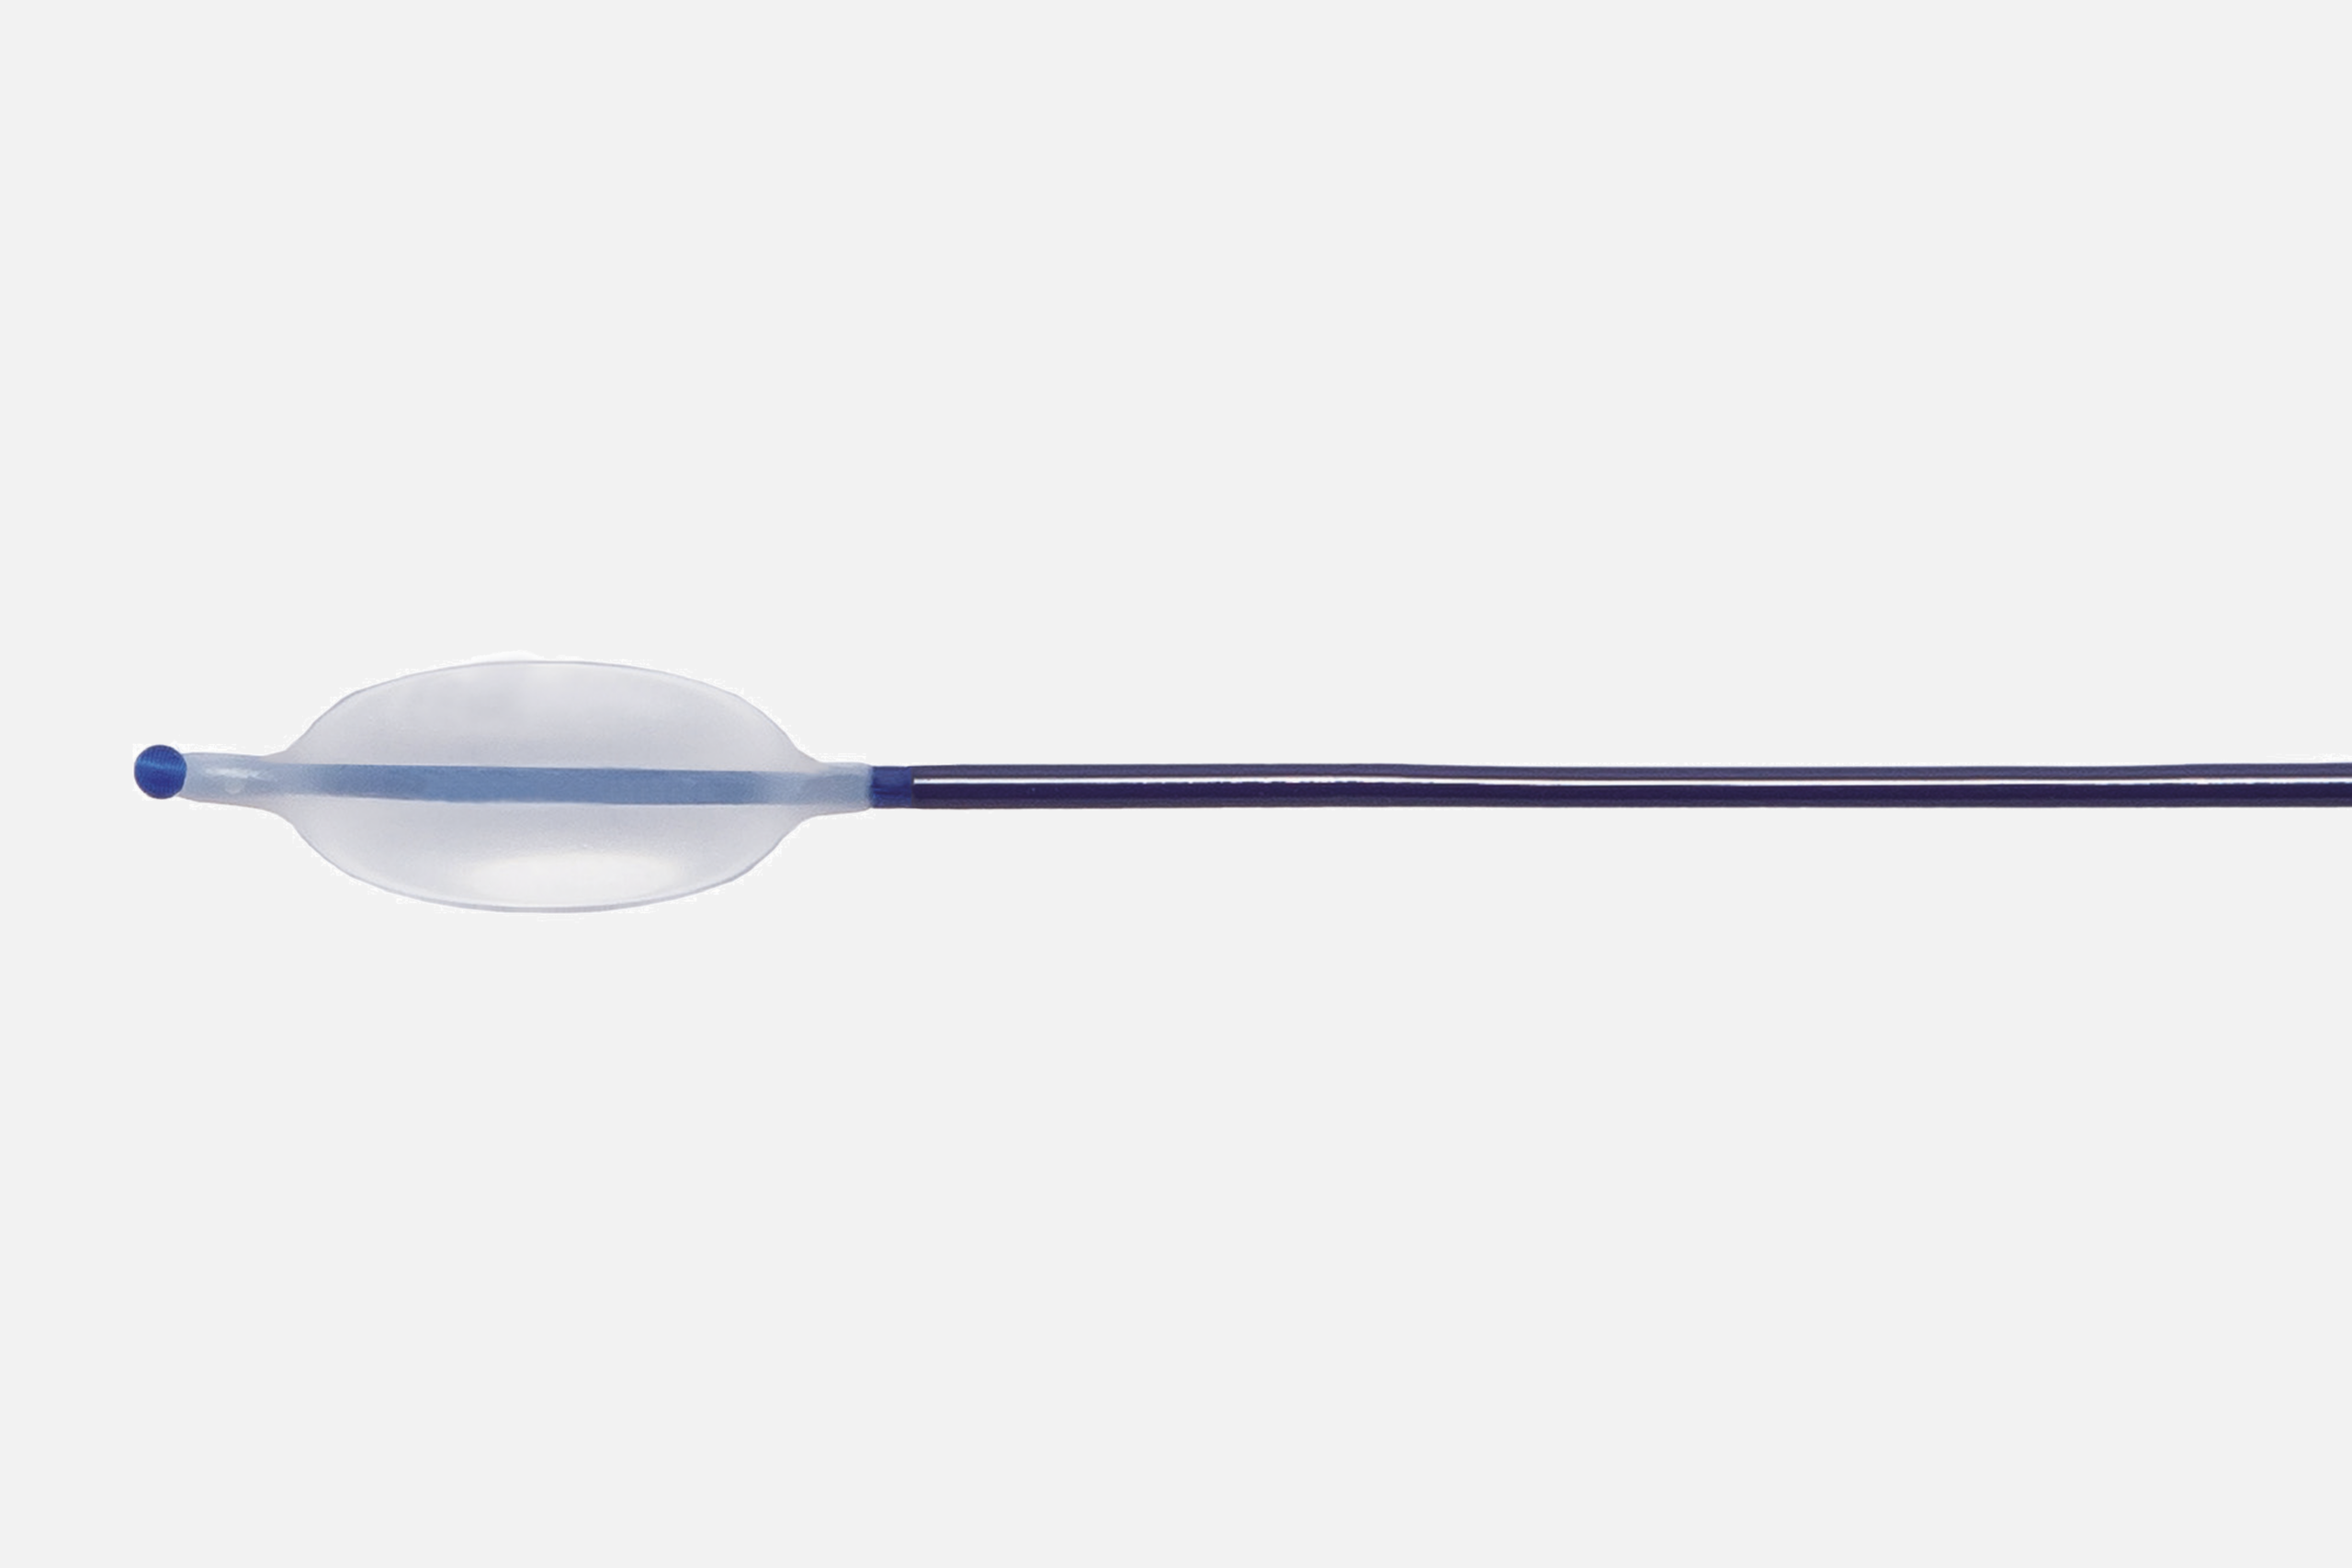

Es un catéter con balón hinchable para adhesiolisis durante la epiduroscopia (IESS). Este dispositivo está diseñado y certificado para su uso junto al catéter guiado por imagen Resascope en el espacio epidural. Éste presenta en su parte distal un balón, que debe inflarse con suero salino accionando la jeringa que encontraremos en el kit y se une al catéter en la parte proximal con una conexión Luer Lock.

Es un catéter con balón hinchable para adhesiolisis durante la epiduroscopia (IESS). Este dispositivo está diseñado y certificado para su uso junto al catéter guiado por imagen Resascope en el espacio epidural. Éste presenta en su parte distal un balón, que debe inflarse con suero salino accionando la jeringa que encontraremos en el kit y se une al catéter en la parte proximal con una conexión Luer Lock.